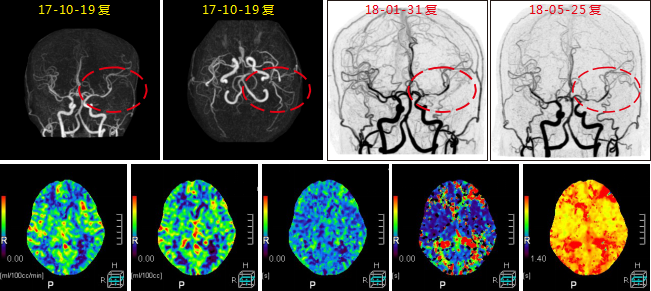

患者術(shù)后復(fù)查腦血管灌注一站式檢查, 腦血管CTA顯示原閉塞的左側(cè)大 腦 中 動(dòng) 脈M 1段 此 次 顯 影 通 暢 , 局 部 中 度 狹 窄 。 腦 灌 注 分 析 顯 示 左 側(cè) 額 葉 及 頂 枕 葉 軟 化 灶 改 變 , 基 本 同 前 ; 原 左 側(cè) 的 大 腦 中 動(dòng) 脈 供 血 區(qū) 大 面 積 灌 注 異 常 較 前 明 顯 改 善 。2 0 1 8 - 1和 2018 - 5月兩次復(fù)查, 都顯示原堵塞血管通暢, 與溶栓后對(duì)比無(wú)明顯變化。

640層寬體探測(cè)器CT為16 cm覆蓋不動(dòng)床一站式神經(jīng)成像, 通過(guò)一次注藥, 一次掃描可以 獲得完整的純動(dòng)脈期、 純靜脈期和腦血流功能灌注成像及動(dòng)態(tài)CT- DSA電影圖像, 每一個(gè)動(dòng) 態(tài) 數(shù) 據(jù) 都 是 在 同 一 時(shí) 相 獲 得 , 同 時(shí) 包 含 了 解 剖 和 功 能 的 信 息 , 通 過(guò) 對(duì) 神 經(jīng) 一 站 式 的 快 速 分 析, 在60 秒內(nèi)就可以完成急性腦卒中的全面評(píng)估。

不動(dòng)床的采集模式避免了螺旋穿梭式灌注帶來(lái)的全器官不在同一時(shí)相采集、 連續(xù)曝光劑 量大的不足; 獨(dú)有的SVD+算法帶來(lái)精準(zhǔn)的灌注結(jié)果, 結(jié)合獨(dú)有的全顱冠狀位和矢狀位的灌 注圖及血管與灌注融合圖像可以清楚顯示梗塞血管及其造成的低灌注區(qū)域, 帶來(lái)精準(zhǔn)的檢查 結(jié)果。

此外, 機(jī)器同時(shí)搭載了雙空間多模型的AIDR 3 D迭代技術(shù), 使得神經(jīng)一站式檢查的劑量 僅需2 - 3 m Sv,造影劑用量?jī)H需40 ml,有效降低了檢查所需的輻射劑量和造影劑用量, 特別 適合需要多次復(fù)查的患者。